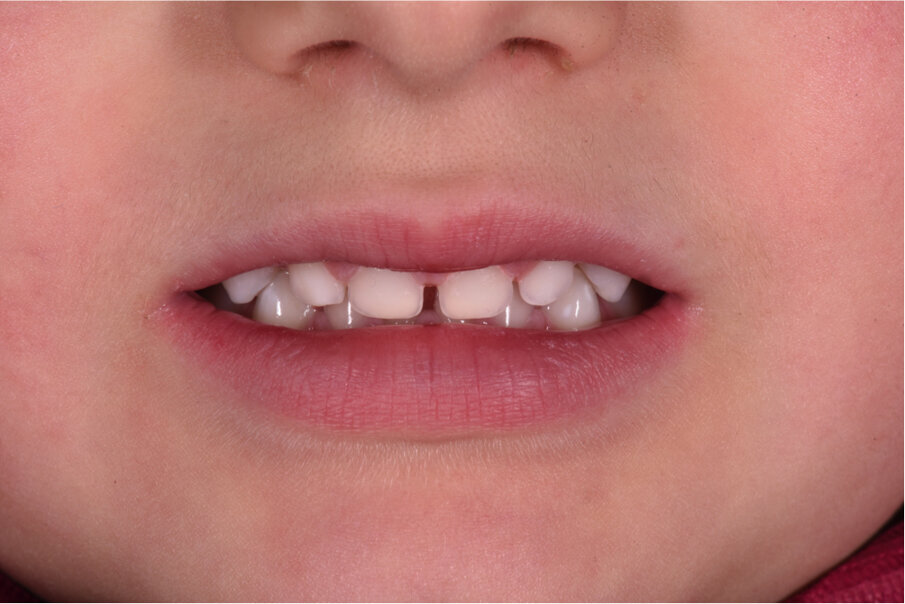

Caso 2 Paziente di anni 4, malocclusione dentale di III Classe, morso crociato monolaterale dx. La paziente viene trattata con dispositivo Amcop TC 2, il quale indossato tutte le notti e 1 ora di pomeriggio in 8 mesi risolve la malocclusione ripristinando il corretto rapporto occlusale; durante la terapia si riscontra un netto miglioramento della respirazione nasale e quindi il ripristino delle normali funzioni respiratorie. Il dispositivo, nei mesi successivi, viene indossato dalla paziente solo la notte per stabilizzare il caso e per guidare la crescita nel miglior modo possibile; all’età di 6 anni la paziente viene sottoposta a check-up ortodontico completo e quindi a panoramica e teleradiografia per poter analizzare anche la previsione di crescita e stabilire un eventuale step elastodontico (Figg. 15-23).

Fig. 15

Fig. 16

Fig. 17

Fig. 18

Fig. 19

Fig. 20

Fig. 21

Fig. 22

Fig. 23